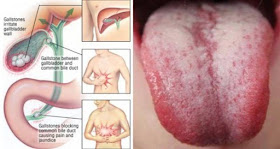

On je zatim dokazao da mnoge hronične degenerativne bolesti potiču od inficiranih zuba bez živaca, od čega su najčešće srčane i cirkulatorne bolesti. On je otkrio jaku povezanost između zuba sa izvađenim živcima i bolestima zglobova, mozga i nervnog sistema.

Nijedan oblik sterilizacije do sada nije bio dovoljno efikasan za rješavanje ovog problema. Infekcija se često prošiti i do vilice, gdje stvara kavitacije iliti pukotine.

Kavitacije su mjesta nezaliječenih kostiju koja često predstavljaju žarište infekcije i gangrene. One nekada nastaju nakon vađenja zuba, ali se javljaju i nakon vađenja zubnog živca.

Može doći do nastanka bolesti srca, bubrega, kostiju i mozga

Ove bakterije zatim mogu da pređu u okolna tkiva i da završe u vašem krvotoku, gdje se prenose na nove lokacije, bilo da su to tkiva ili organi.

Skoro sve hronične degenerativne bolesti su povezane sa ovom stomatološkom procedurom, uključujući:

Srčane bolesti

Bolesti bubrega

Artritis, reumatske bolesti i bolesti zglobova

Neurološke bolesti (npr. ALS)

Autoimune bolesti (npr. Lupus)